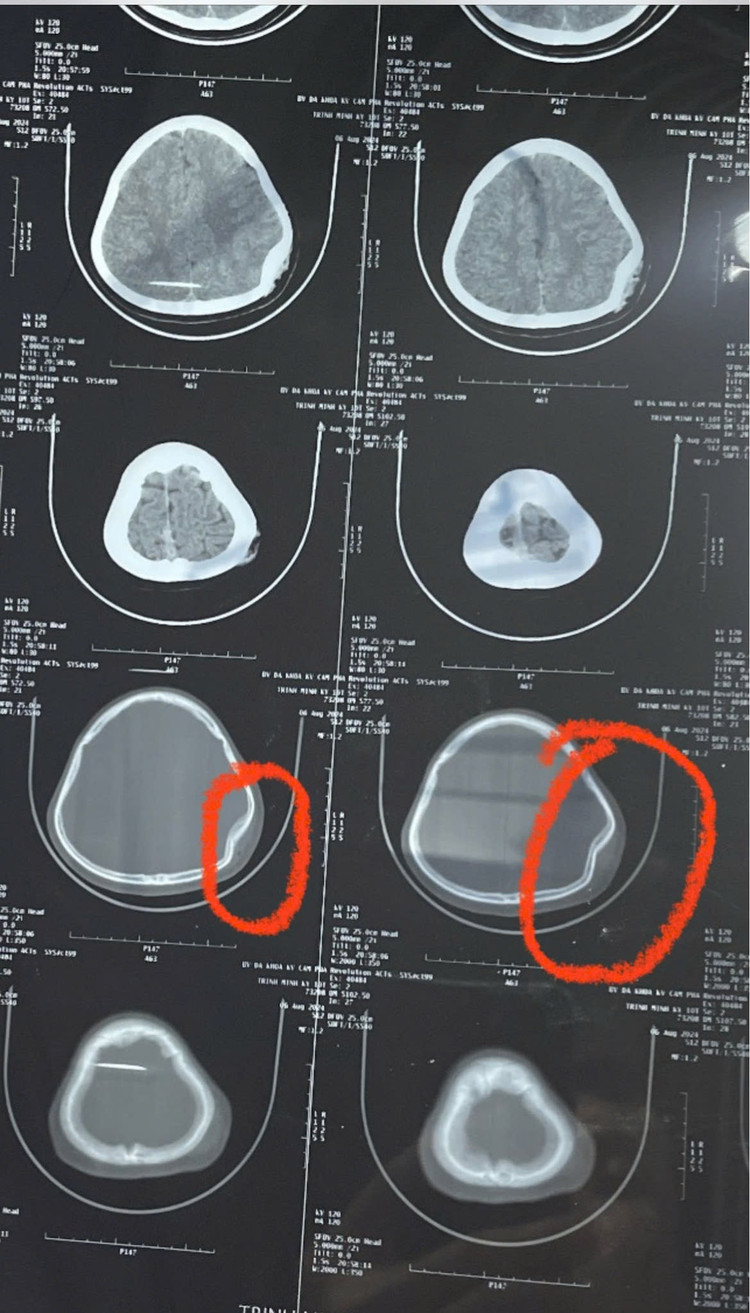

Các bác sĩ đã kiểm tra toàn trạng, làm các xét nghiệm và chẩn đoán hình ảnh cần thiết. Kết quả cho thấy, bệnh nhân có sưng nề vùng đỉnh trái (kích thước khoảng 3x2 cm) kèm vết thương rách da (kích thước khoảng 1cm), có trầy xước da vùng cổ, vai trái (kích thước khoảng 10x7cm), sưng nề, trầy xước da gối trái (kích thước khoảng 7x5cm). Kết quả hình ảnh CT.Scanner sọ não cho thấy vỡ lún xương đỉnh trái kèm phù nề tụ khí mô mềm vị trí tổn thương. Chẩn đoán chấn thương sọ não. Bệnh nhân K. được cấp cứu, băng cầm máu vết thương và chuyển lên Bệnh viện Đa khoa tỉnh để tiếp tục điều trị.

| Hình ảnh CTScanner sọ não của bệnh nhân K cho thấy vỡ lún xương đỉnh trái kèm phù nề tụ khí mô mềm vị trí tổn thương. Ảnh BVCC |